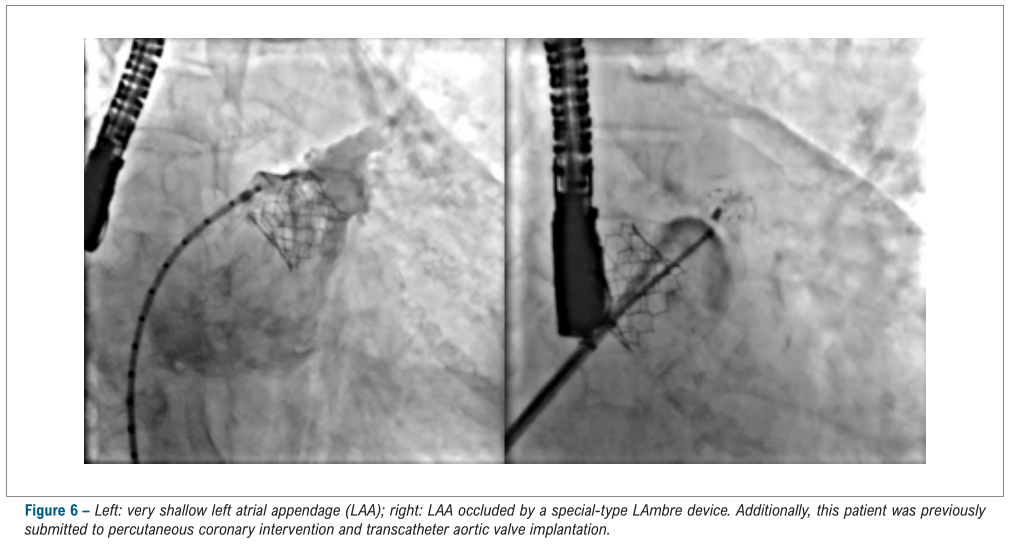

LAmbre™植入成功率为100%, 所有患者均无明显残余分流(> 5mm),仅4例患者(7.8%)在手术结束时存在较小残余分流(<5mm)。手术即刻并发症包含2例心包积液,1例器械栓塞(成功抓捕),未出现其他不良事件。此外,3位患者存在卵圆孔未闭(PFO),术者成功通过2例患者的PFO通道进入左心房实施封堵,另外一例患者心耳为反鸡翅形态,经PFO路径导致鞘管轴向不佳,最终改为实施房间隔穿刺进入左心房行封堵术。

LAmbre™术中影像